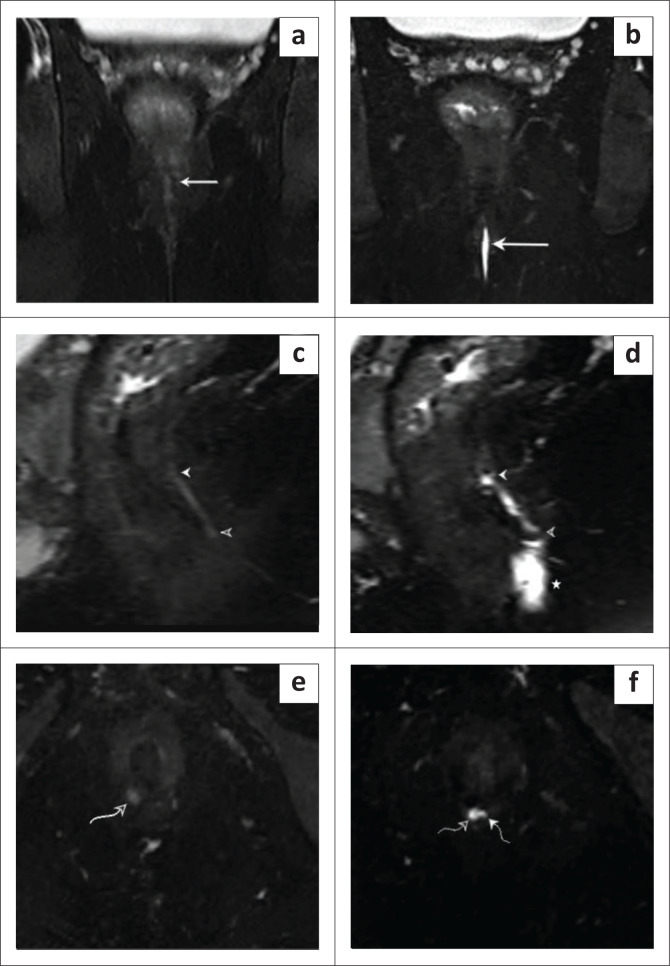

Background: Magnetic resonance fistulography (MRF) is a key non-invasive imaging technique for mapping perianal fistulas before surgery. The instillation of aqueous jelly, like ultrasound gel, enhances the signal-to-noise ratio, improving image quality and MRF accuracy. This low-cost approach improves accessibility, especially in resource-limited settings, while ensuring patient comfort and safety.

Objectives: To determine the impact of aqueous jelly on the accuracy of MRF in identifying fistulous tracts, internal openings, secondary ramifications and abscesses and the quality of visualisation of MRF with and without jelly instillation.

Method: A cross-sectional study at Krishna Rajendra and Cheluvamba Hospitals, Mysore (October 2024-March 2025), included 40 patients with perianal fistulas. Magnetic resonance fistulography was performed using a 1.5 Tesla uMR 570 system, without and with 5 mL - 7 mL of sterile aqueous jelly instilled percutaneously. MRI findings were compared with intraoperative results. Data were analysed using Statistical Package for the Social Sciences (SPSS) to assess sensitivity, specificity and accuracy.

Results: Magnetic resonance fistulography with gel improved visualisation, identifying internal openings in 92.5% of cases (vs. 24% without gel) and secondary tracts in 40% (vs. 17.5%). The accuracy compared to surgery was 97.5% for internal openings, 95% for secondary tracts, 97.5% for abscesses and 100% for supralevator extension.

Conclusion: Aqueous jelly instillation enhances MRF accuracy, improving fistula visualisation and aiding in preoperative planning. This technique reduces recurrence and incontinence risk and supports more accurate surgical interventions.